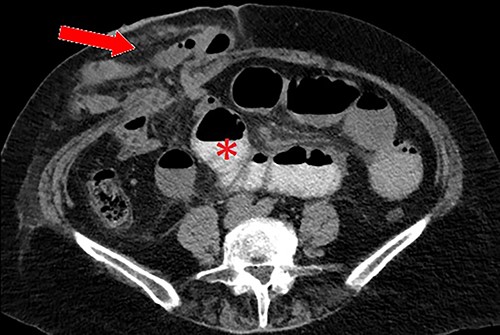

Clinical presentation of this diverticulum, if not asymptomatic, is gastrointestinal bleeding, bowel obstruction or inflammation/perforation [2]. Attempting to diagnose MD using CT imaging in patients with generic symptoms of abdominal pain or bleeding has an impressively low yield – often indistinguishable from adjacent loops of small bowel – thus a majority in adult patients are detected incidentally during surgery [3]. In the present case, after confirming the finding operatively, a close retrospective review of the CT identified the diverticulum (Fig. 2).

Axial CT scan demonstrating the MD (circled) arising from the anti-mesenteric aspect of the ileum within the parastomal hernia, identified after close retrospective review of imaging post operatively.